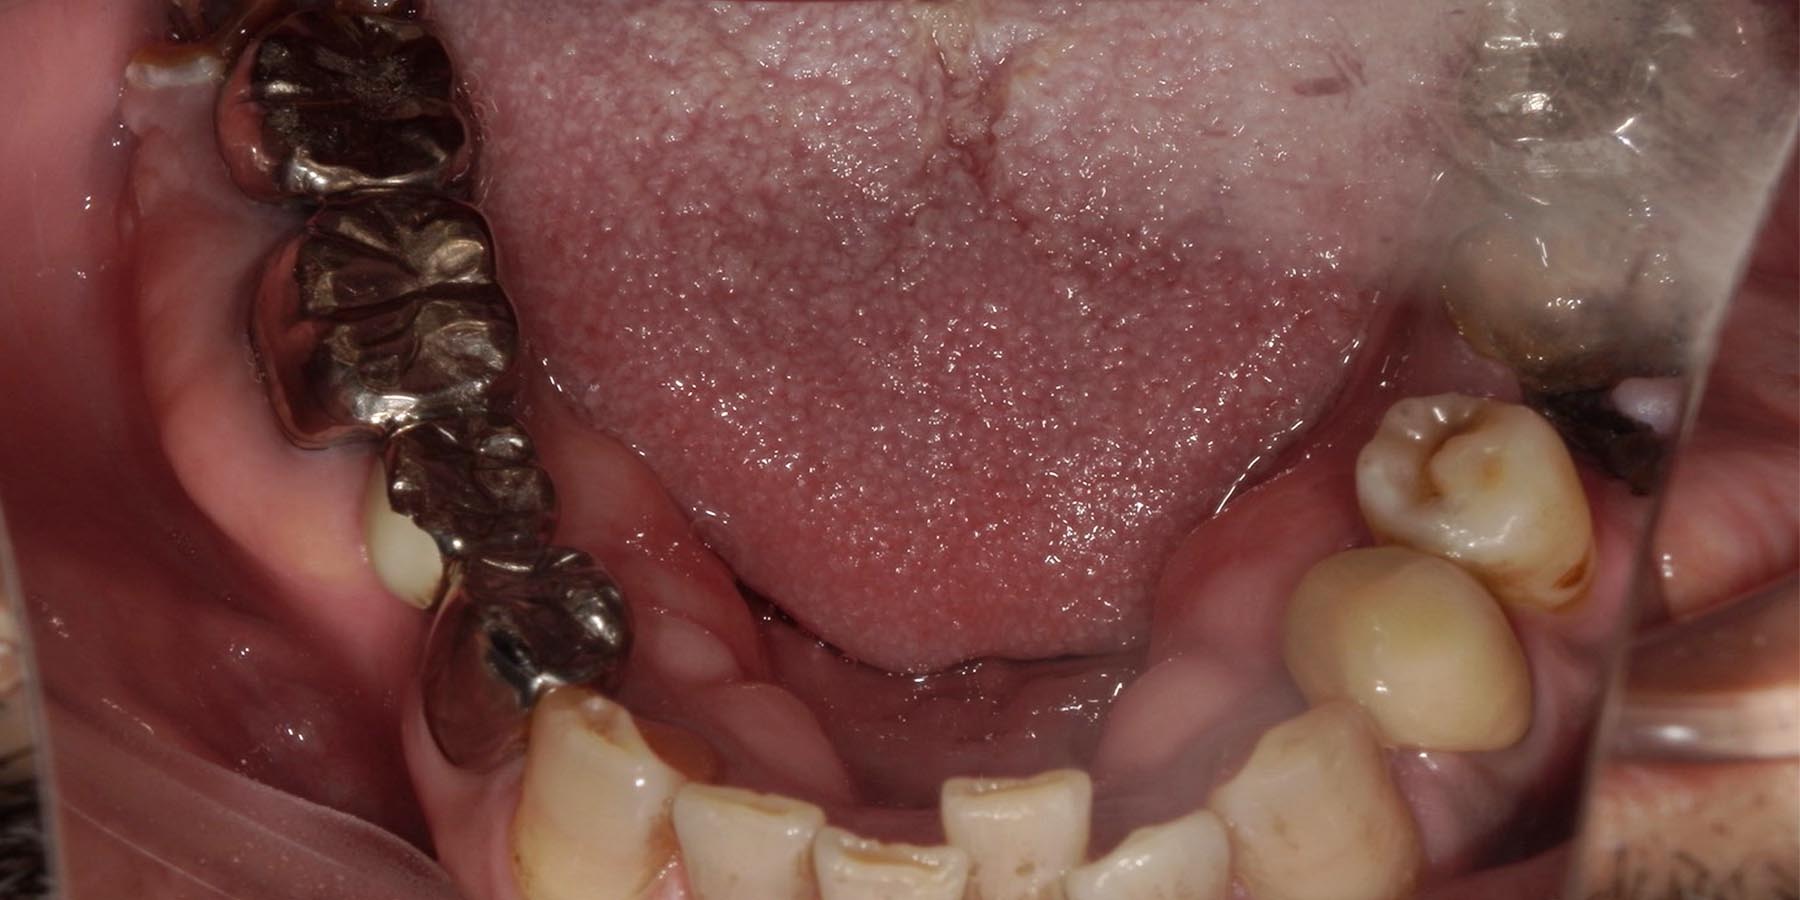

治療前

治療前(CT)